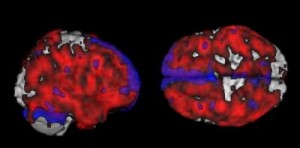

Brain Composite Image 2: Two views of a composite image of the brains analyzed in the study compare the average increases in amyloid-beta deposits in volunteers with a maternally or paternally inherited risk of Alzheimer's, compared to counterparts with no family history of dementia. Red highlights the regions with more amyloid among 14 volunteers with a maternally inherited risk, while blue shows the regions with more amyloid among 14 volunteers with a paternally inherited risk. Purple denotes higher amyloid deposits in both risk groups. (Credit: Lisa Mosconi, Ph.D., Mony J. de Leon, Ed.D.)

The study examined 42 healthy individuals, including 14 whose mothers had Alzheimer’s, 14 whose fathers had Alzheimer’s, and 14 counterparts with no family history of the disease. On average, the first group of volunteers showed a 15 percent higher burden of amyloid-beta deposits than those with a paternal family history, and a 20 percent higher burden of the protein clumps than those with no familial risk factors.